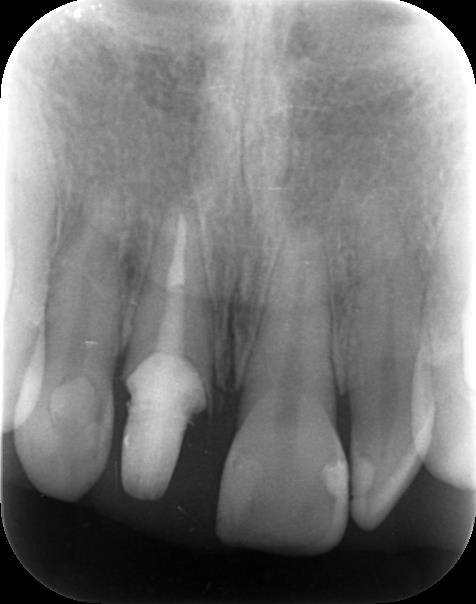

根管治療後の土台コア装着後のレントゲン写真